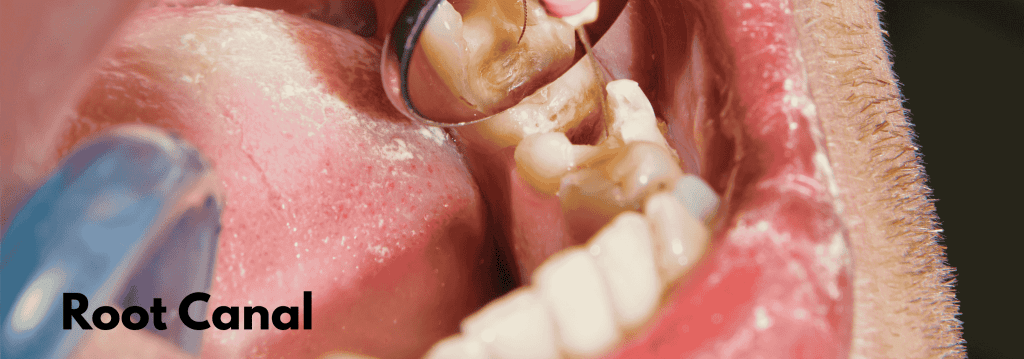

In endodontic procedures, achieving a hermetic seal within the root canal system is essential to prevent reinfection and ensure long-term success. The MANI Flare Finger Spreaders are designed to make this critical stage of treatment — gutta percha condensation — precise, efficient, and predictable.

The MANI Flare Finger Spreaders are primarily used in the lateral condensation of gutta percha during root canal obturation. Below are some common clinical applications:

🔹 1. Conventional Root Canal Therapy (RCT)

After cleaning and shaping, the spreader is used to create space for accessory gutta percha cones alongside the master cone. This ensures dense lateral compaction, reducing voids and improving the seal of the root canal system.